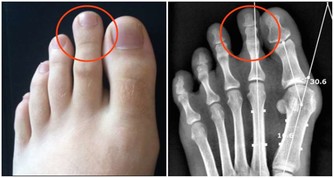

排腎毒吃黃瓜有效果:

腎臟是人體內最重要的排毒器官,不僅過濾掉血液中的毒素通過尿液排出體外,

還擔負著保持人體水分和鉀鈉平衡的作用,控制著和許多排毒過程相關的體液循環。

黃瓜、櫻桃等蔬果有助於腎臟排毒。

黃瓜的利尿作用能清潔尿道,有助於腎臟排出泌尿系統的毒素。